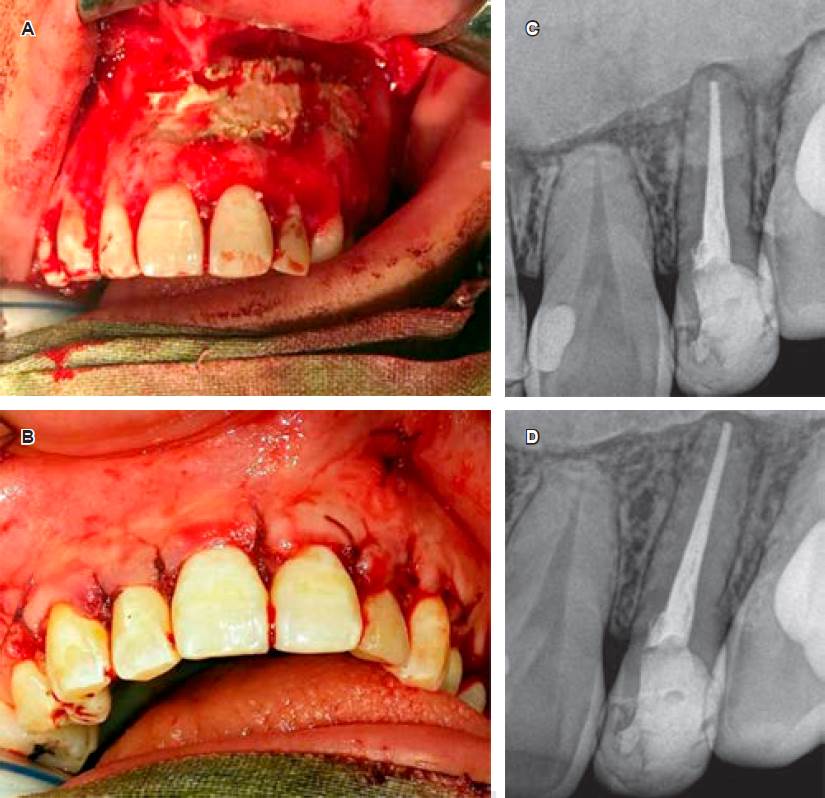

4) Remoción de remanente lesional y colocación de sustituto óseo en forma diferida: a los ocho meses de tratamiento descompresivo, a petición de la paciente, se procedió a realizar lavado quirúrgico de la lesión y remoción de remanente quístico bajo anestesia general. Se procedió a realizar una incisión amplia tipo festoneada que se extendió desde el incisivo lateral derecho hasta el segundo molar izquierdo. Posteriormente a la separación del mucoperiostio, se efectuó el curetaje del lecho quístico, desprendimiento de su cápsula y coloca ción de sustituto óseo sintético inyectable en pasta, compuesto de fosfato dicálcico deshidratado en 55%, fosfato tricálcico en 45% con poder bioconductor para relleno del gran colapso óseo residual postquistectomía (Figura 5A y B), el mismo fue recubierto con membrana de colágena reabsorbible. Se retiró el drenaje que se había colocado en primera cirugía de diagnóstico. Por último, se procedió a reposicionar el colgajo mucoperióstico y la confección de una sutura a puntos separados. El diagnóstico histopatológico de la lesión enucleada confirmó el diagnóstico inicial (quiste maxilar inflamatorio). La Figura 5C fue obtenida en forma inmediata a la colocación del sustituto óseo. Durante su evolución, se realizó un seguimiento clínico y radiográfico del caso con resultados altamente satisfactorios (en la Figura 5D se puede observar el estado de la pieza problema y los tejidos peridentarios normales con relación al sustituto óseo). A la fecha, la paciente lleva dos años de control, observando ausencia de recidivas y vitalidad pulpar conservada de las piezas previamente involucradas.

Figura 5 Remoción del remanente quístico y colocación de sustituto óseo. A-B) Muestran el colgajo amplio realizado para el abordaje y el lecho quirúrgico postquistectomía rellenado con el sustituto óseo, el cual fue debidamente compactado en el interior del tejido óseo. Luego de la colocación de membrana reabsorbible, se realizó la reposición del colgajo mucoperióstico y la sutura correspondiente. C) Radiografía postquirúrgica inmediata donde puede observarse el material de relleno como una masa densa radiopaca. D) El control radiográfico al año muestra normalidad de los tejidos dentarios y peridentarios, y persistencia del sustituto óseo.